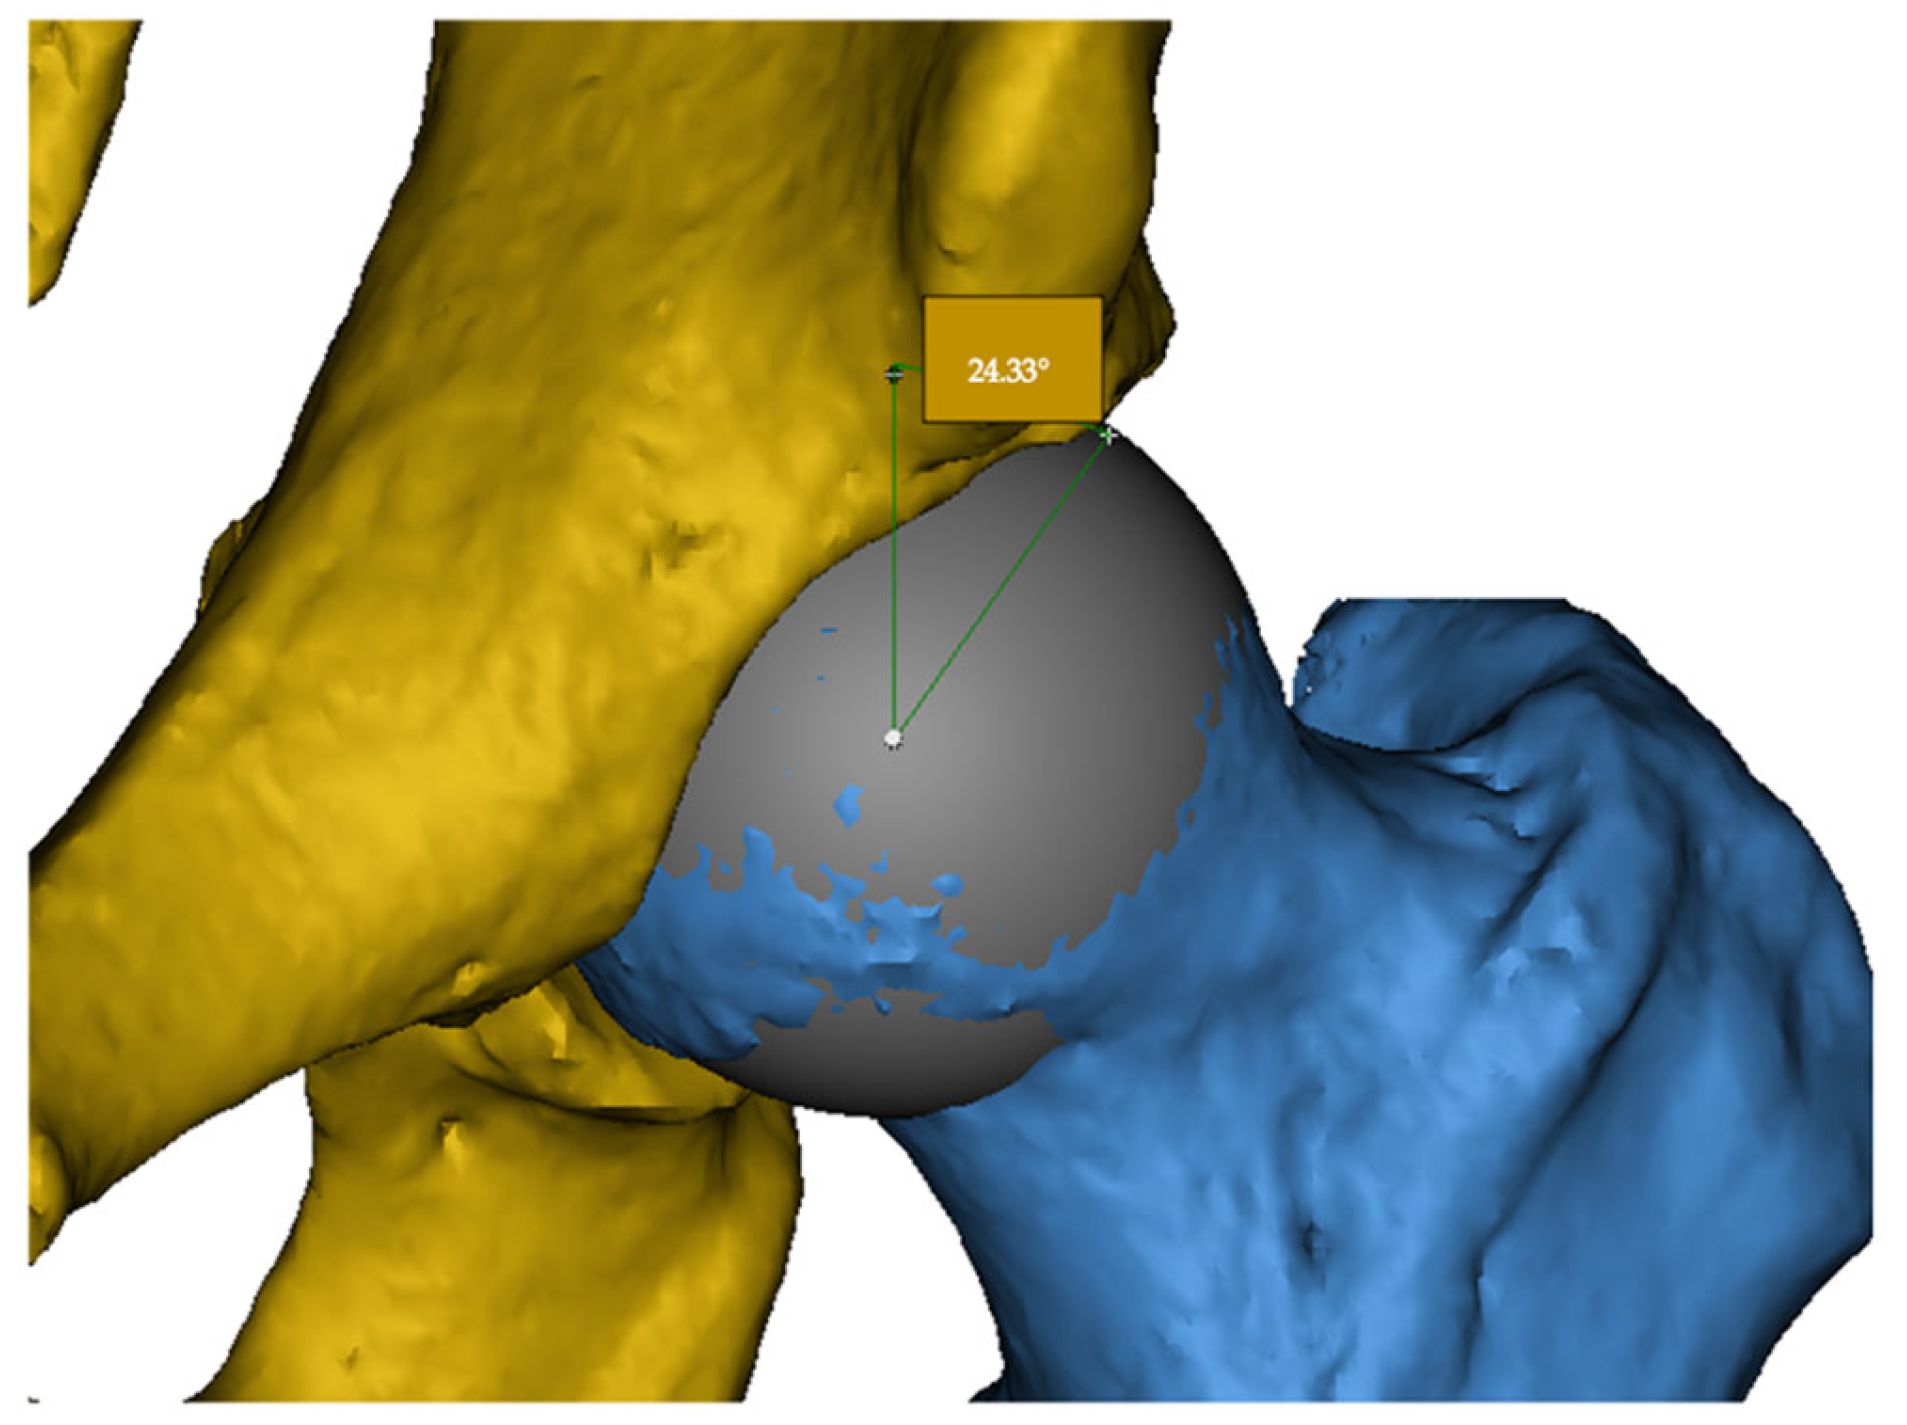

The LCEA is defined as the angle between a vertical line passing through the center of the femoral head and a line drawn from the center to the lateral edge of the acetabular roof. This angle quantifies the degree of acetabular coverage over the femoral head. Excessive LCEA values suggest pincer-type impingement, whereas low values may indicate acetabular dysplasia (Figure 1).

Figure 1. Measurement of the lateral center-edge angle (LCEA) on a 3D CT reconstruction. The acetabulum is shown in yellow and the femoral head in blue. The example demonstrates an LCEA of 24.33°.